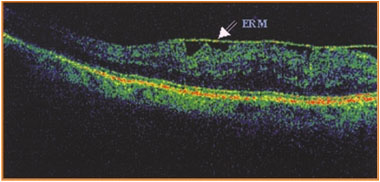

Precision Diagnosis (OCT)

The diagnosis is confirmed by Optical Coherence Tomography (OCT). This is a painless test that gives us a cross-section of the fundus, allowing us to see the thickness of the membrane and the swelling it causes, with millimetre precision.